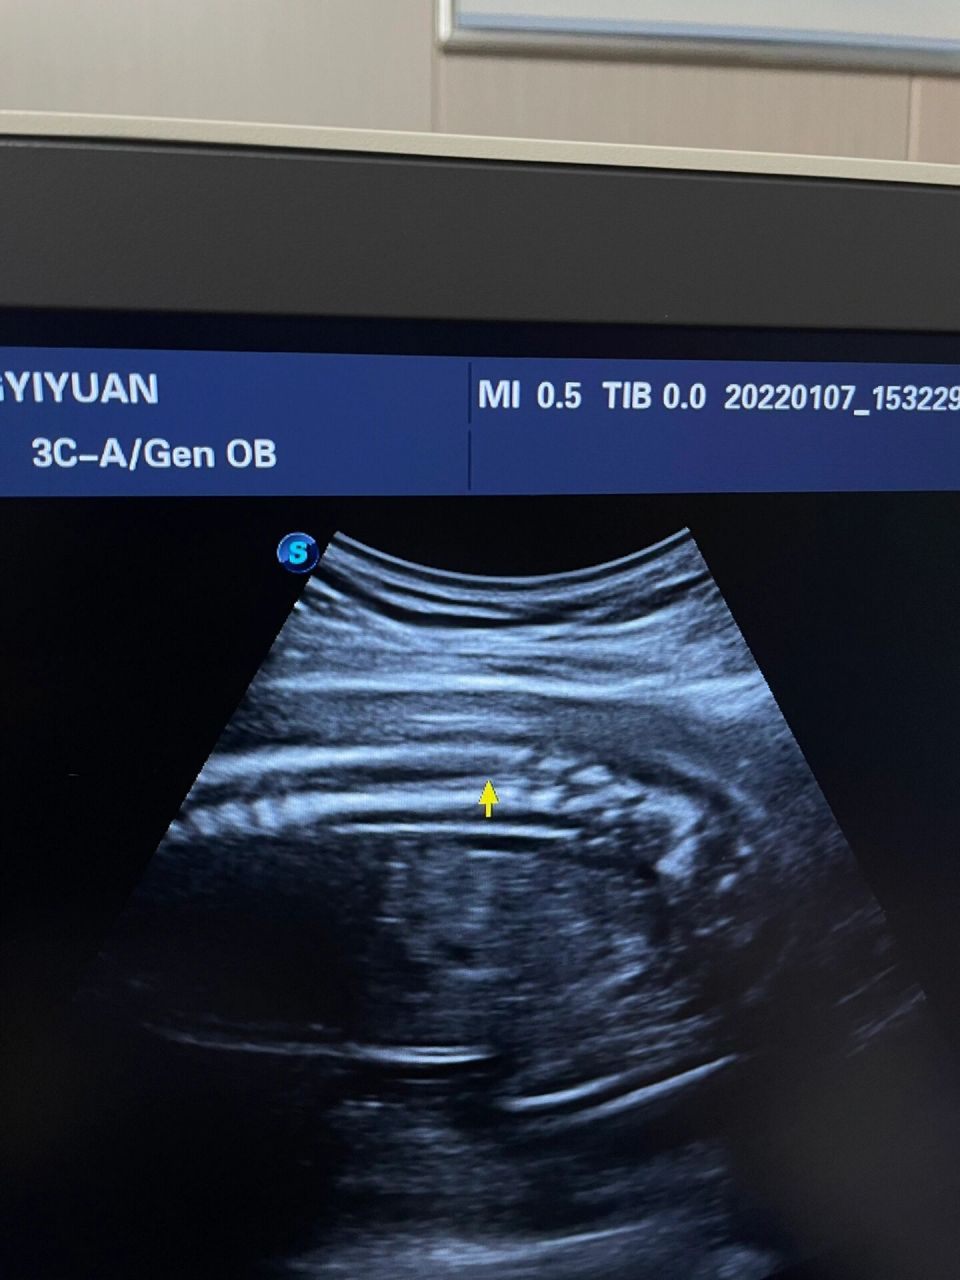

胎儿脊髓圆锥偏低,终于涨上去了 26周省妇幼做的,四维脊髓圆锥偏低

超声胎儿脊髓圆锥 脊髓圆锥声像图有两个特点——黑尖白细 ●黑尖